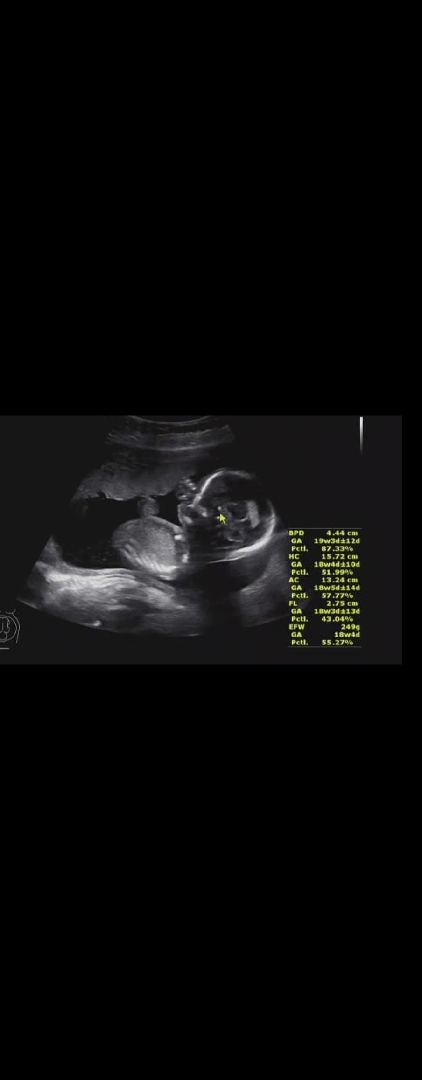

오늘은 18주 3일이 됐어요! 초음파를 보는데 손을 빨고 있더라구요ㅎㅎㅎ 얼마나 예쁘던지❣️ 한명은 이렇게나 잘보여주고 한명은 몇주째 등돌리고 있어서 보기가 쉽지않네요ㅎㅎㅎㅎ 다다음주에는 정밀초음파를 본다는데 별문제없이 이번에도 잘 통과되었으면 좋겠어요 ㅎㅎ 임산하면서 늘 느끼는거지만 엄마되는것이 쉽지않은거같아요! 몸도 점점 힘들어지고 이벤트들도 많고.. 그래서 울기도하고, 어쩔때는 행복해서 웃기도하고 참 감정이 하루에도 왔다갔다하는 듯 하네요! ㅎㅎ 또 툭툭 거리는 태동을 느낄때면 엄청 신기해요!!! 오늘은 여기서 툭 다른 날은 저기서 툭 이제 아이들이 조금 더 자라면 배로 뚫고나올것같은 귀욤뽀짝 발모양도 볼수있겠죠?ㅎㅎㅎ 그리고 전 요즘 하루하루가 금방금방 가는 것 같아서 조금은 아쉬워지는 것 같아요! 아이가 태어나면 몸으로 경험되었던 것들을 못느끼니깐 이런 경험들이 신기하고 소중하고 그러네요ㅎㅎㅎ 초산이라 그럴까요ㅎㅎㅎㅎ 빌리 가족 맘님들❣️ 모두모두 힘내시고 예쁜 아가 만날때까지 건강해요 우리>< 힘내보아용 화이팅💙💙

손가락 빨고있는 모습 너무 사랑스럽네요❤️ 저두 담주면 18주되어가는데 어서 태동 느껴보고싶어요~태동느껴지면 조금 더 맘이 안정될 거 같아요ㅎㅎ